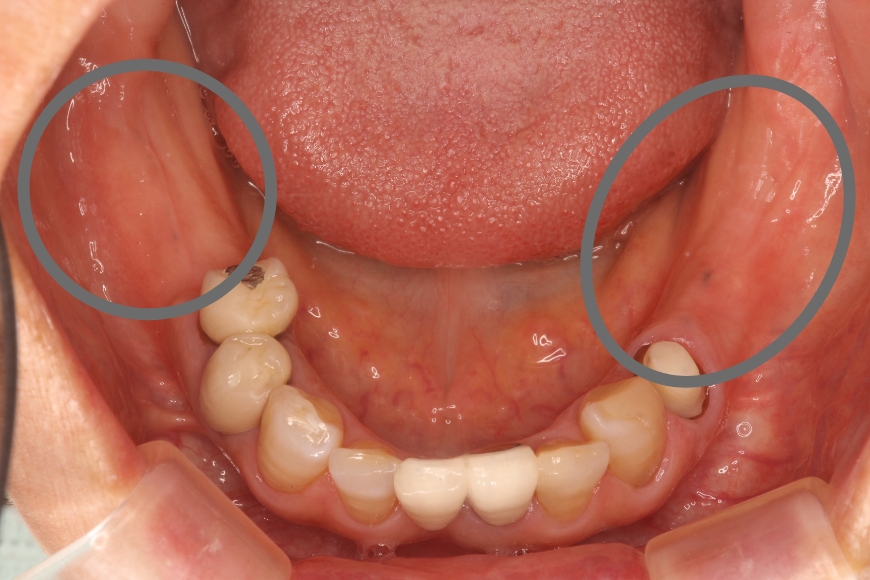

50代女性 左右の奥歯へのインプラント治療

治療前

治療後

治療内容 下の左右の奥歯が無く、食事がうまくできないことを主訴に来院されました。

左右の奥歯に2本ずつインプラント治療を行いました。奥歯でしっかりと噛めるようになりました。

治療期間・回数 治療期間:約6ヶ月

通院回数:10回程度

治療費用(総額)

1,760,000

(1本440,000円×4本分。時期や手法により異なる場合があります。)

副作用・リスク ・インプラント埋入手術直後は、不快感、痛みを感じることがあります。

・下顎のインプラントは下歯槽神経に障害を及ぼした場合、数か月の知覚異常が生じる場合があります。

・インプラント周囲炎(インプラントの歯周病)などのトラブルを防ぐため、定期的なメンテナンスを行う必要があります。